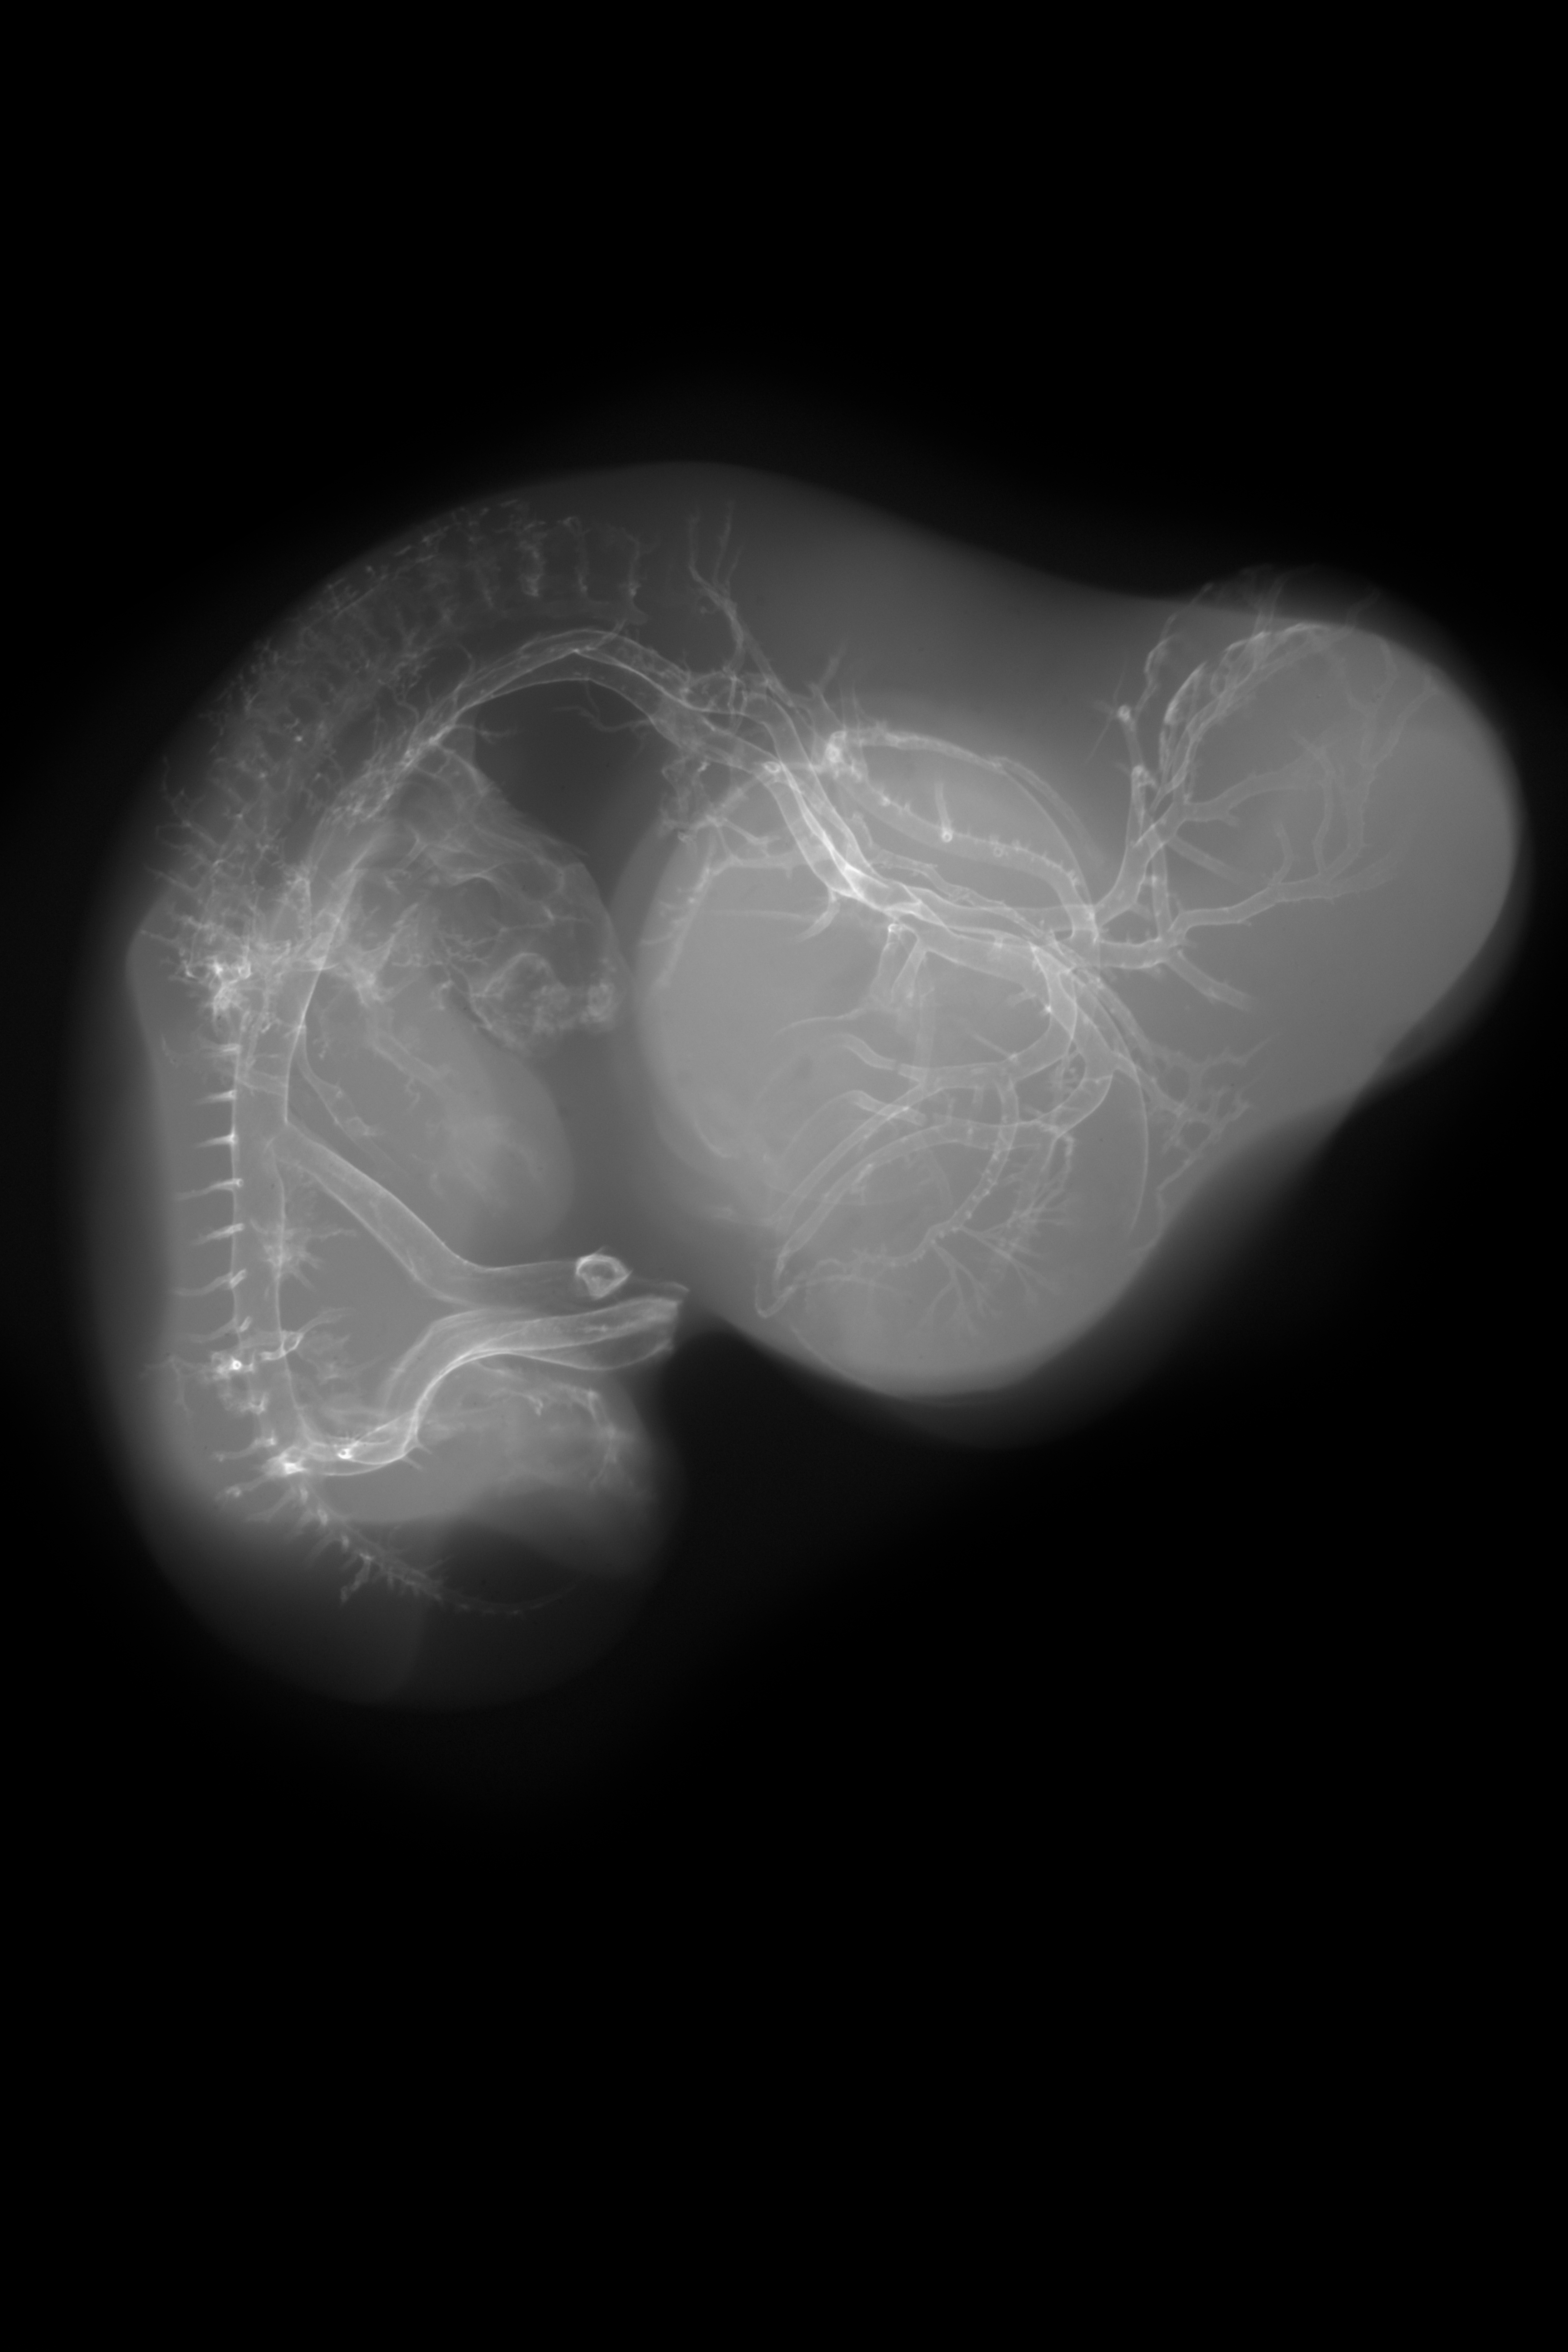

X-Ray Micrographs